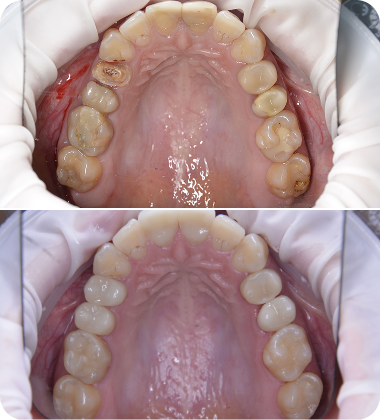

Протезирование зубов, реставрация композитным материалом

Работу провел Аришев Артем Денисович

Протезирование

Аришев А.Д.